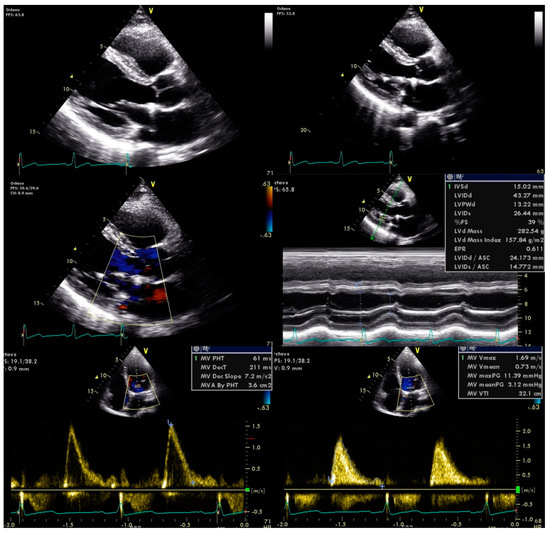

Antimicrobial therapy was promptly initiated with vancomycin and gentamicin for six weeks. He was also referred to the cardiothoracic surgery department for mitral valve plasty, with no further complications observed (Figure 3).

Figure 3. Transthoracic echocardiography post mitral valve plasty.